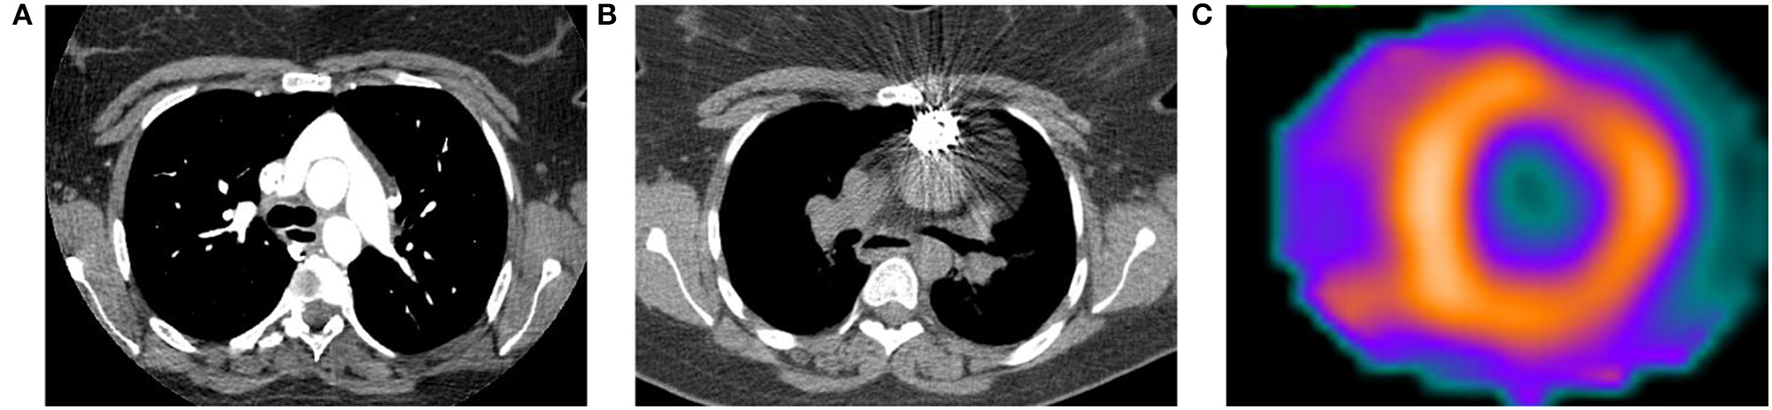

Single-photon emission computed tomography (SPECT) utilizes multiple different radiotracers to evaluate cardiac perfusion and function. Analogous to PET, patients with PH will have evidence of thickening, enlargement, and metabolic derangement in the RV. The most commonly used radiotracers in modern cardiac SPECT are mitochondrial imaging agents (e.g., 99mTc-sestamibi), and their increased uptake in the RV is reflective of both increased RV mass and increased energy production and use (90). Figure 4 is from a patient with a pulmonary artery stenosis and increased 99mTc-sestamibi uptake in the RV.

Figure 4

Computed tomography (CT) and 99mTc-sestamibi single-photon emission computed tomography (SPECT) images from a 23-year-old woman with history of D-transposition of the great arteries (D-TGA) status-post repair. (A) Transaxial CT angiogram image demonstrating the characteristic appearance of the pulmonary artery and aorta after repair of D-TGA. (B) Non-contrast CT acquired at time of SPECT shows a stent in the pulmonary artery that was placed after the patient developed severe pulmonary artery stenosis. (C) Short axis SPECT image shows normal radiotracer distribution in the left ventricle with extension of uptake into the visualized portion of the right ventricle, consistent with pulmonary hypertension.